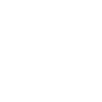

- 전악임플란트

- 흔들리는 치아, 이젠 안녕!

- 전악임플란트

- 전악임플란트

- 흔들리는 치아, 이젠 안녕!

- 임플란트